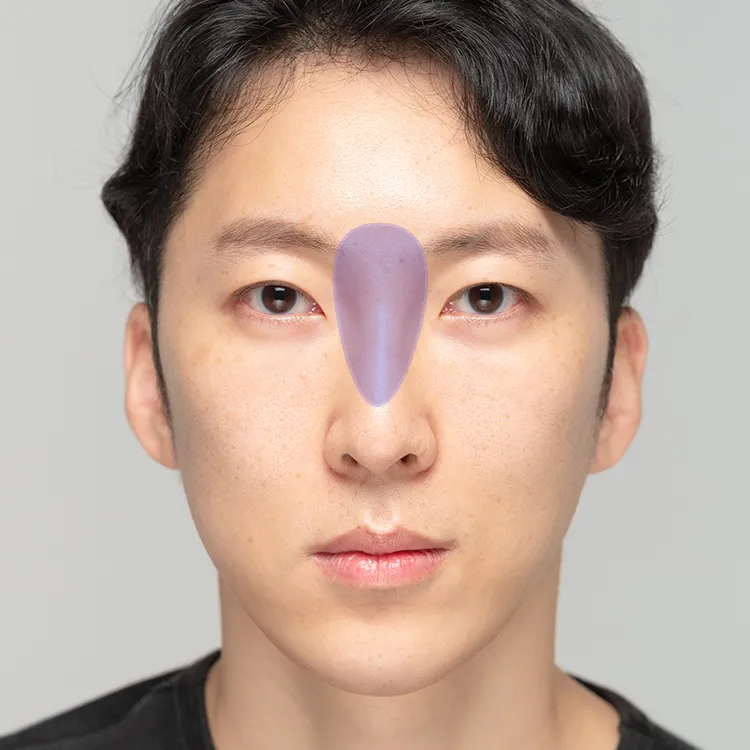

Cystic

Comedonal

Nodular

Papular

Pustular

Folliculitis

Scars

Pores